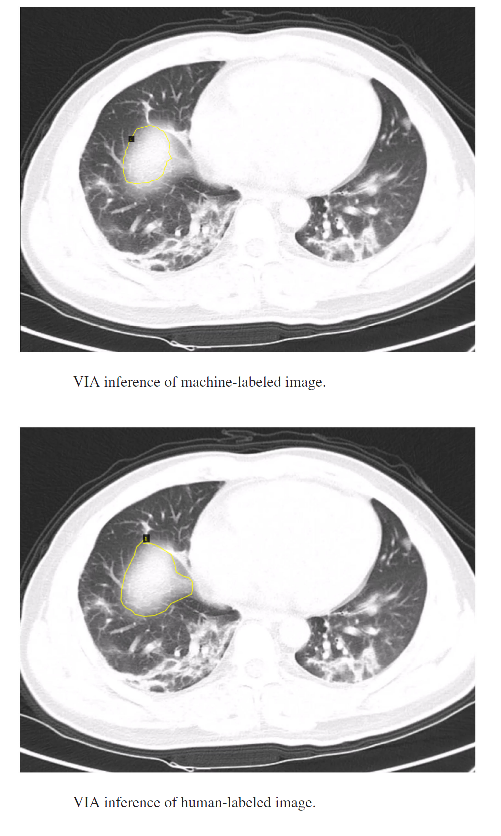

我们测试了我们的方法,目的是为新冠病毒感染区域自动生成计算机标签。

机器生成标签和人工标注标签的结果如下所示。可以看出,自动注释引擎生成的合成标签质量相当好,可用于重新训练对象检测模型或生成更多可用于不同任务的注释数据。